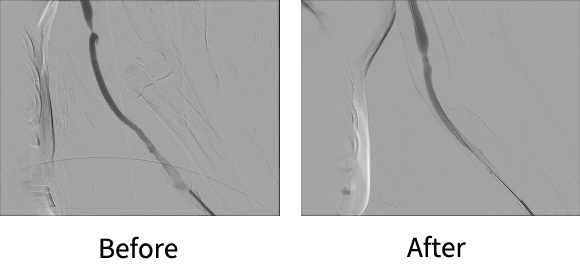

기존 혈관조영장비를 보완해 보다 선명한 영상과 치료를 가능케한 최첨단 AI 탑재 장비